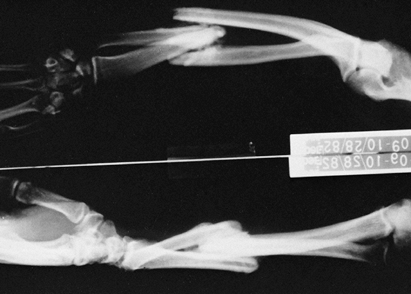

Spasticity can mask underlying motor control (Fig. 67.1).

Figure 67.1.

This series of tracings records by electrogoniometer the maximum arc and frequency of elbow flexion—extension movement in a patient with traumatic brain injury. The first tracing is maximal effort before placement of a block. The second tracing shows improvement after a bupivacaine motor point block of the brachioradialis. Further improvement is noted immediately after bupivacaine block of the biceps and 30 minutes after block of the brachioradialis. After the biceps block has been allowed to set up, further improvement is noted. The blocks were used to demonstrate that there was volitional motor control in the elbow flexors that was previously masked by the spastic response of the muscles to movement. The blocks also preview the improvement to be gained by fractional lengthening of the elbow flexors. (With permission from Hisey MS, Keenan MAE. Orthopaedic Management of Upper Extremity Dysfunction Following Stroke or Brain Injury. In Green DP, Hotchkiss RN, Pederson WC, eds. Operative Hand Surgery, 4th ed. New York: Churchill Livingstone, 1998:287.) |